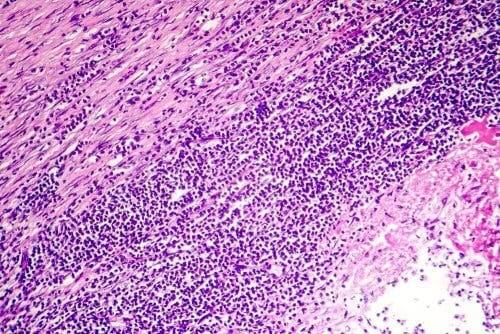

Pericarditis henviser til betændelse i perikardium (hjertesækken), en sækkeformet membran, der omgiver hjertet. Denne membran har to lag og indeholder mellem disse lag en lille mængde væske. Dette er et smøremiddel, der gør, at de to lag kan glide frem og tilbage.

- Kronisk pericarditis opstår som et resultat af fortykkelse af perikardium eller en ophobning af væske. Det varer mere end seks uger og kan føre til svigt i højre ventrikel. Dette er ødemer i maveregionen, pretibialområdet og anklerne. Kronisk pericarditis opstår, når der dannes fibrøst væv rundt om hjertet, komprimerer det og øger trykket i de årer, der fører blod til det. Således stagnerer pericardiumvæsken og ophobes i andre dele af kroppen på vej ud.